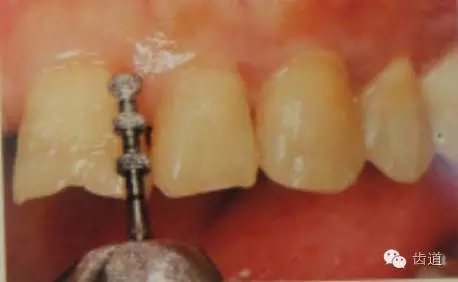

1、唇面預備:先用定深車針定出定深溝,再換合適車針磨除剩余的釉質。

唇面磨除的量依據所用貼面材料及牙齒的變色程度而定。

如下圖:

預備齦下邊緣之前要先排齦,之后選用圓頭錐形車針磨除牙體到所設計的邊緣位置。